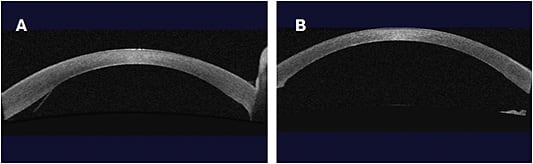

CORNEAL CROSS-LINKING

Corneal collagen cross-linking has been a critical development for corneal surgeons and our patients. Long available outside the United States, cross-linking with the iLink platform (Glaukos) was approved by the FDA for use in 2016. Most insurance companies now cover both the drugs (Photrexa Viscous [riboflavin 5’-phosphate in 20% dextran ophthalmic solution] and Photrexa [riboflavin 5’-phosphate ophthalmic solution], Glaukos) and the cross-linking procedure when performed with the iLink platform.

Epi-off cross-linking has been shown to be effective at preserving vision and corneal integrity. The procedure halts progression in 92%-100% of cases.1 Patients treated with cross-linking maintain long-term corneal stability for at least 10 years.2,3 For our patients, cross-linking can help avoid progression to costly specialty lenses and, most importantly, avoid the risks associated with penetrating keratoplasty (PK).4 Historically, up to 21% of patients with progressive keratoconus undergo a PK procedure, with more than half requiring multiple transplants within 20 years.5,6 While corneal transplantation has also improved in recent years, we would still like to avoid this end-stage treatment.

A recent simulation model suggests that cross-linking reduces the rate of PK by 26%, with patients spending 28 fewer years in the advanced stages of keratoconus.4 Cross-linked patients have lower anxiety and better vision- and health-related quality of life after cross-linking.7,8 In my experience, it’s empowering for patients to know they have done everything they could to prevent further progression.

New developments in cross-linking are on the horizon as well. We are learning more about how to use genetic testing to better guide follow-up of close relatives of keratoconus patients. Additionally, a Phase 3 clinical trial of the iLink system for epi-on cross-linking recently met its primary endpoint of a difference of ≥1.0 D mean change in Kmax between treatment and control arms from baseline to month 6, setting the stage for an epi-on FDA submission next year.